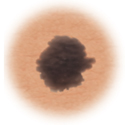

Normal mole.

Moles (nevi)

Small skin marks caused by pigment-producing cells in the skin. Moles can be flat or raised, smooth or rough, and some contain hair. Most moles are dark brown or black, but some are skin-colored or yellowish. Moles can change over time and often respond to hormonal changes.

Most moles are benign and no treatment is needed. Some benign moles may develop into skin cancer (melanoma). See below for signs.